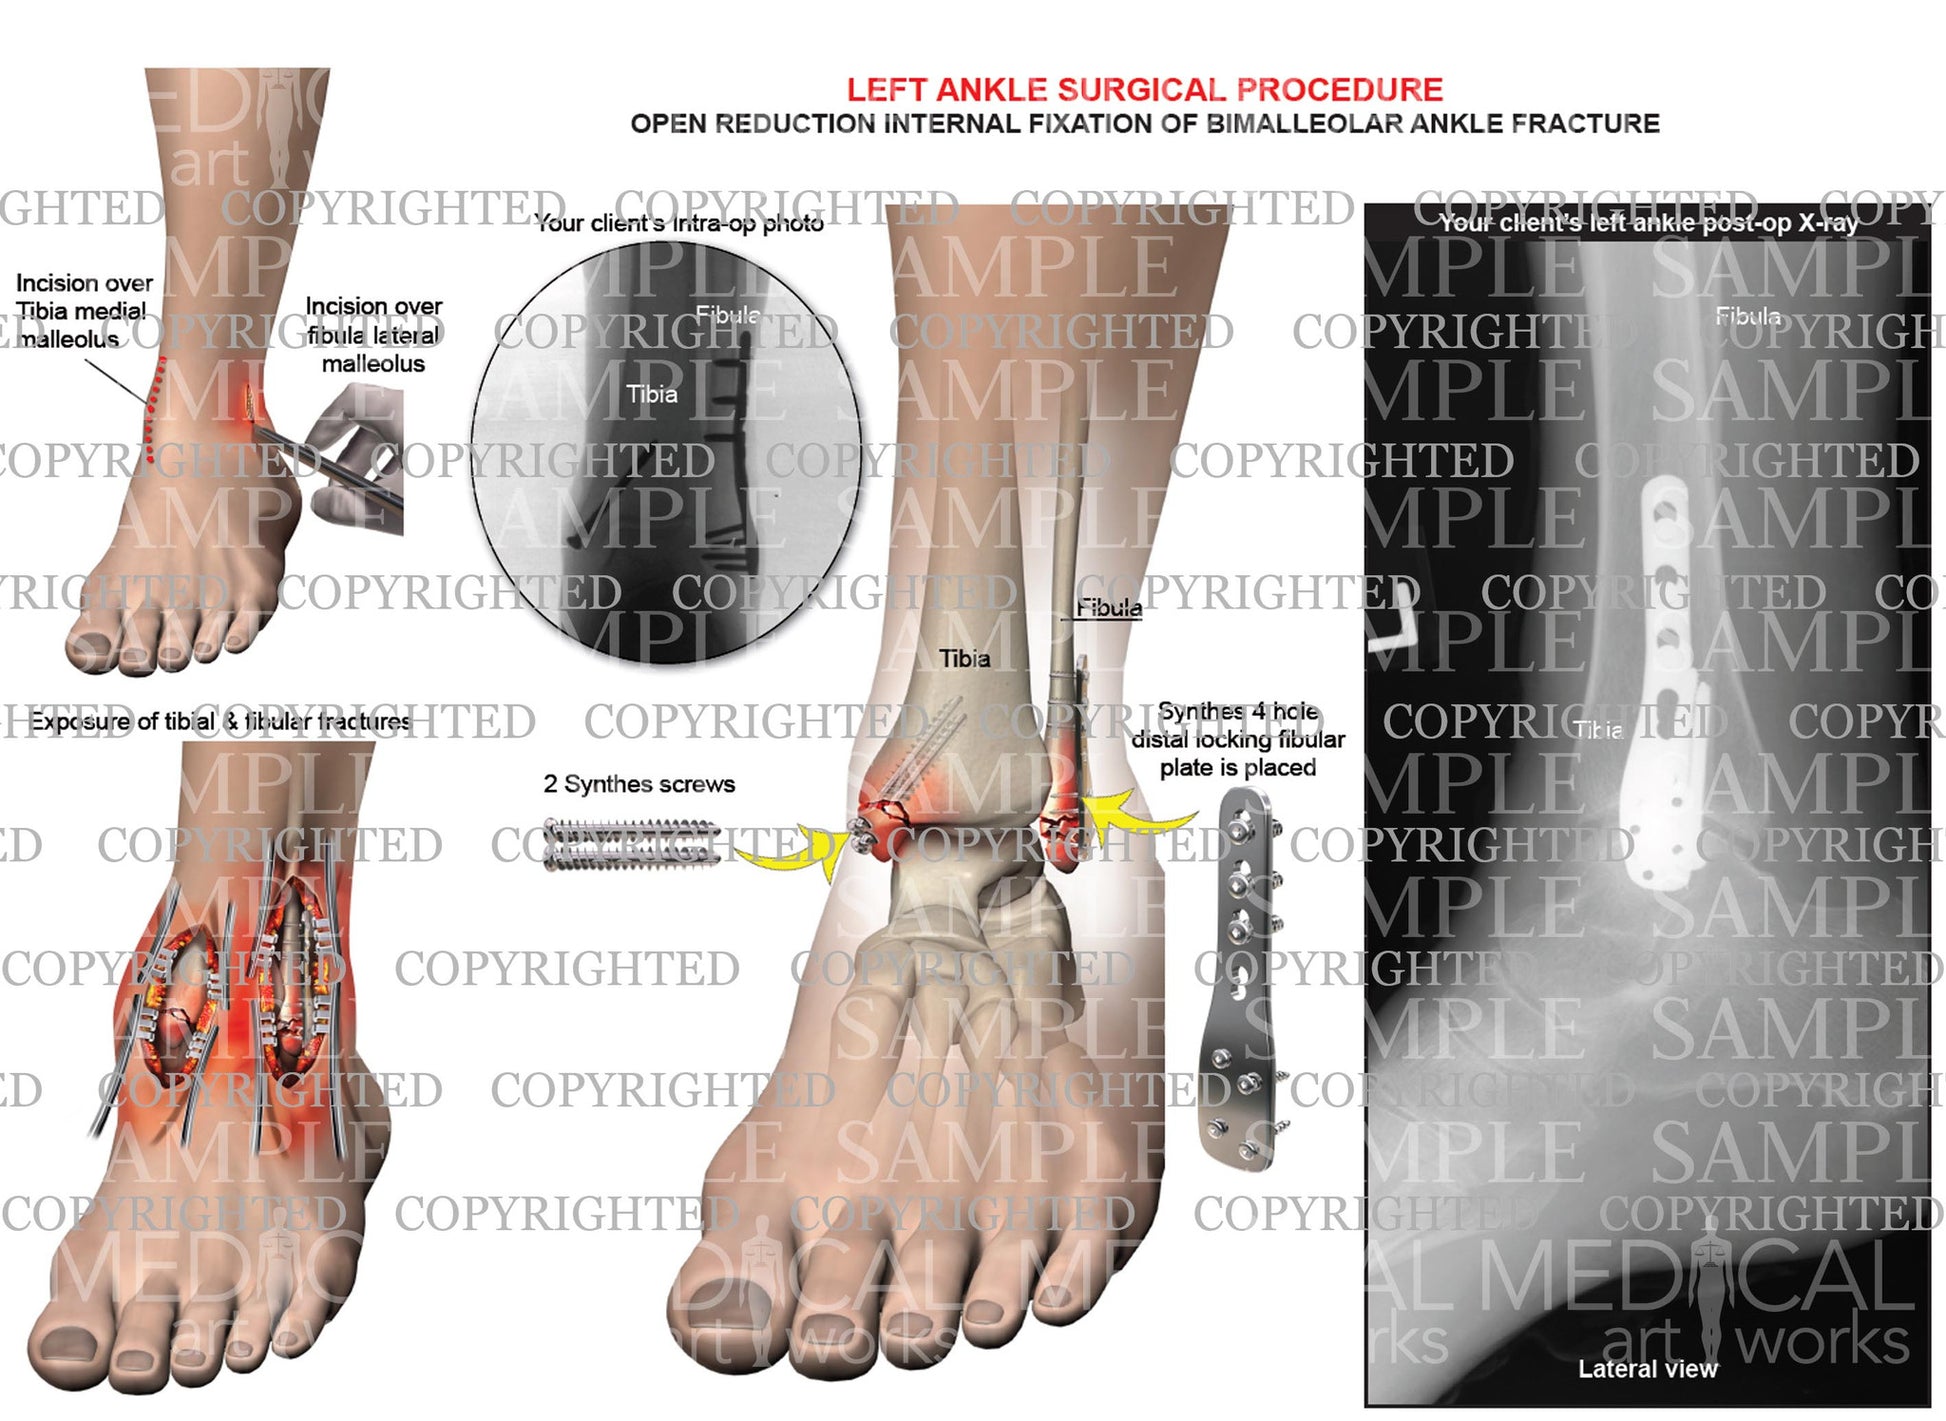

Left ankle and tibia bimalleolar fracture -ORIF

Left ankle and tibia bimalleolar fracture -ORIF

Open reduction internal fixation of bimalleolar ankle fracture. Synthes 4 hole distal locking fibular plate is placed, 2 Synthes screws. Add you own client's post-op x-ray.